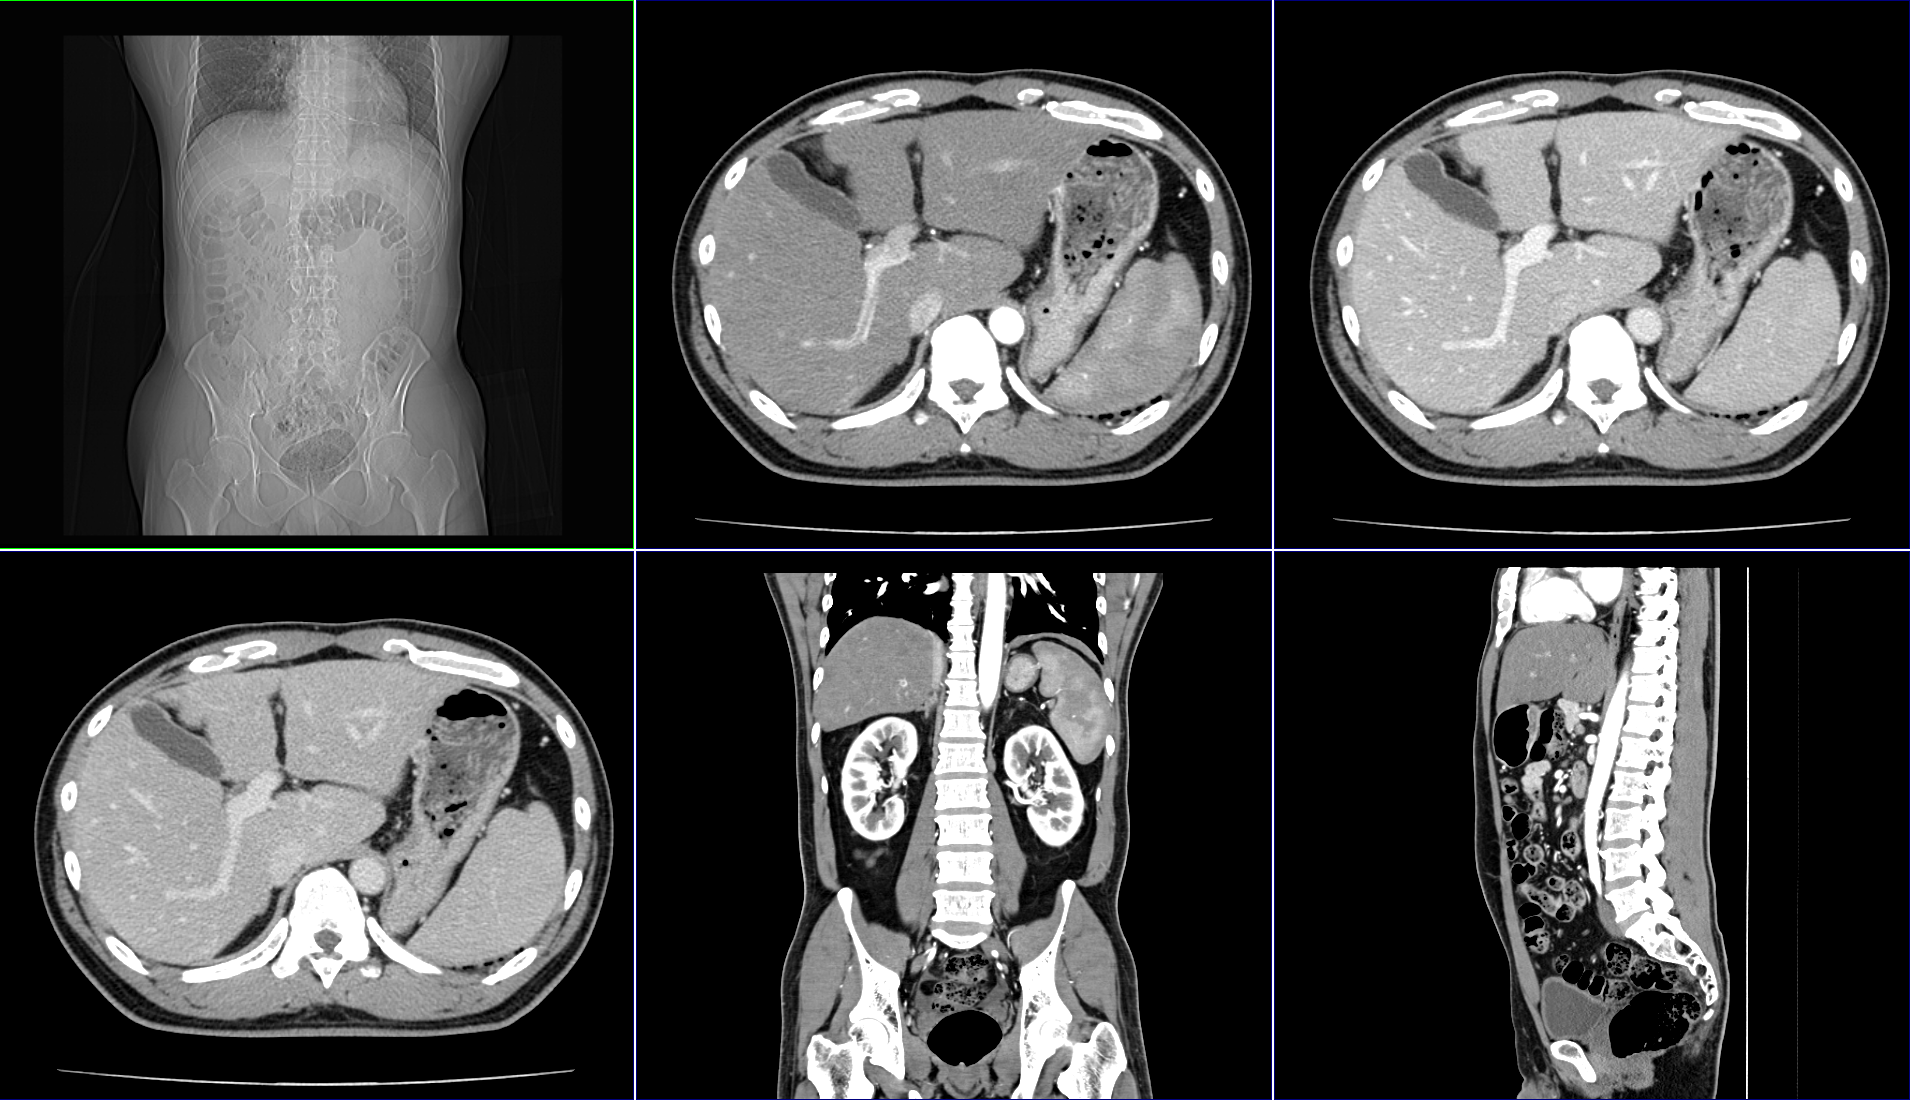

| 造影CT検査 |

造影剤を使用して撮影します。血管や病変部位など、より詳しい情報が得られます。 この情報をもとに、3D画像等の画像を作ることも可能です。 |